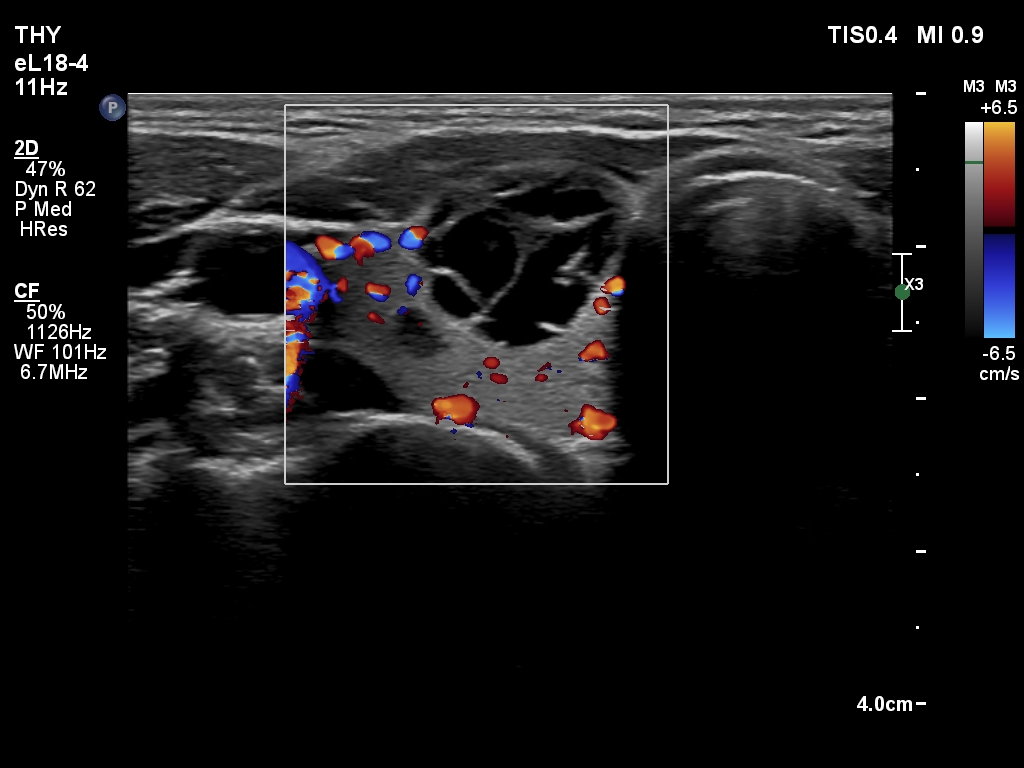

Ultrasonography. The thyroid was echonormal. There was a cystic nodule in the right lobe. The lesion had spongiform portions. The nodules presented all three possible signs of an extrathyroidal extension. There was a minimally hypoechoic nodule in the left lobe.

- Great proportion of benign nodule presents signs of a possible extrathyroidal extension because these features are non-specific, this is particularly true for cystic nodules located at the edge of a lobe. The liquid produced often bulges the surface of the thyroid. The contour of this nodule was abutting and bulging and the thyroid capsule was discontinuous.